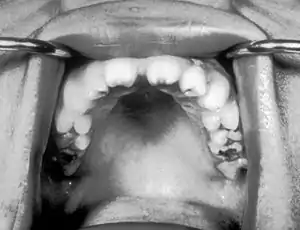

Hutchinson's teeth

Hutchinson's teeth[1] is a sign of congenital syphilis. Affected people have teeth that are smaller and more widely spaced than normal and which have notches on their biting surfaces. It is named after Sir Jonathan Hutchinson, an English surgeon and pathologist, who first described it.

| Notched incisors known as Hutchinson's teeth which are characteristic of congenital syphilis | |

Hutchinson's teeth form part of Hutchinson's triad.